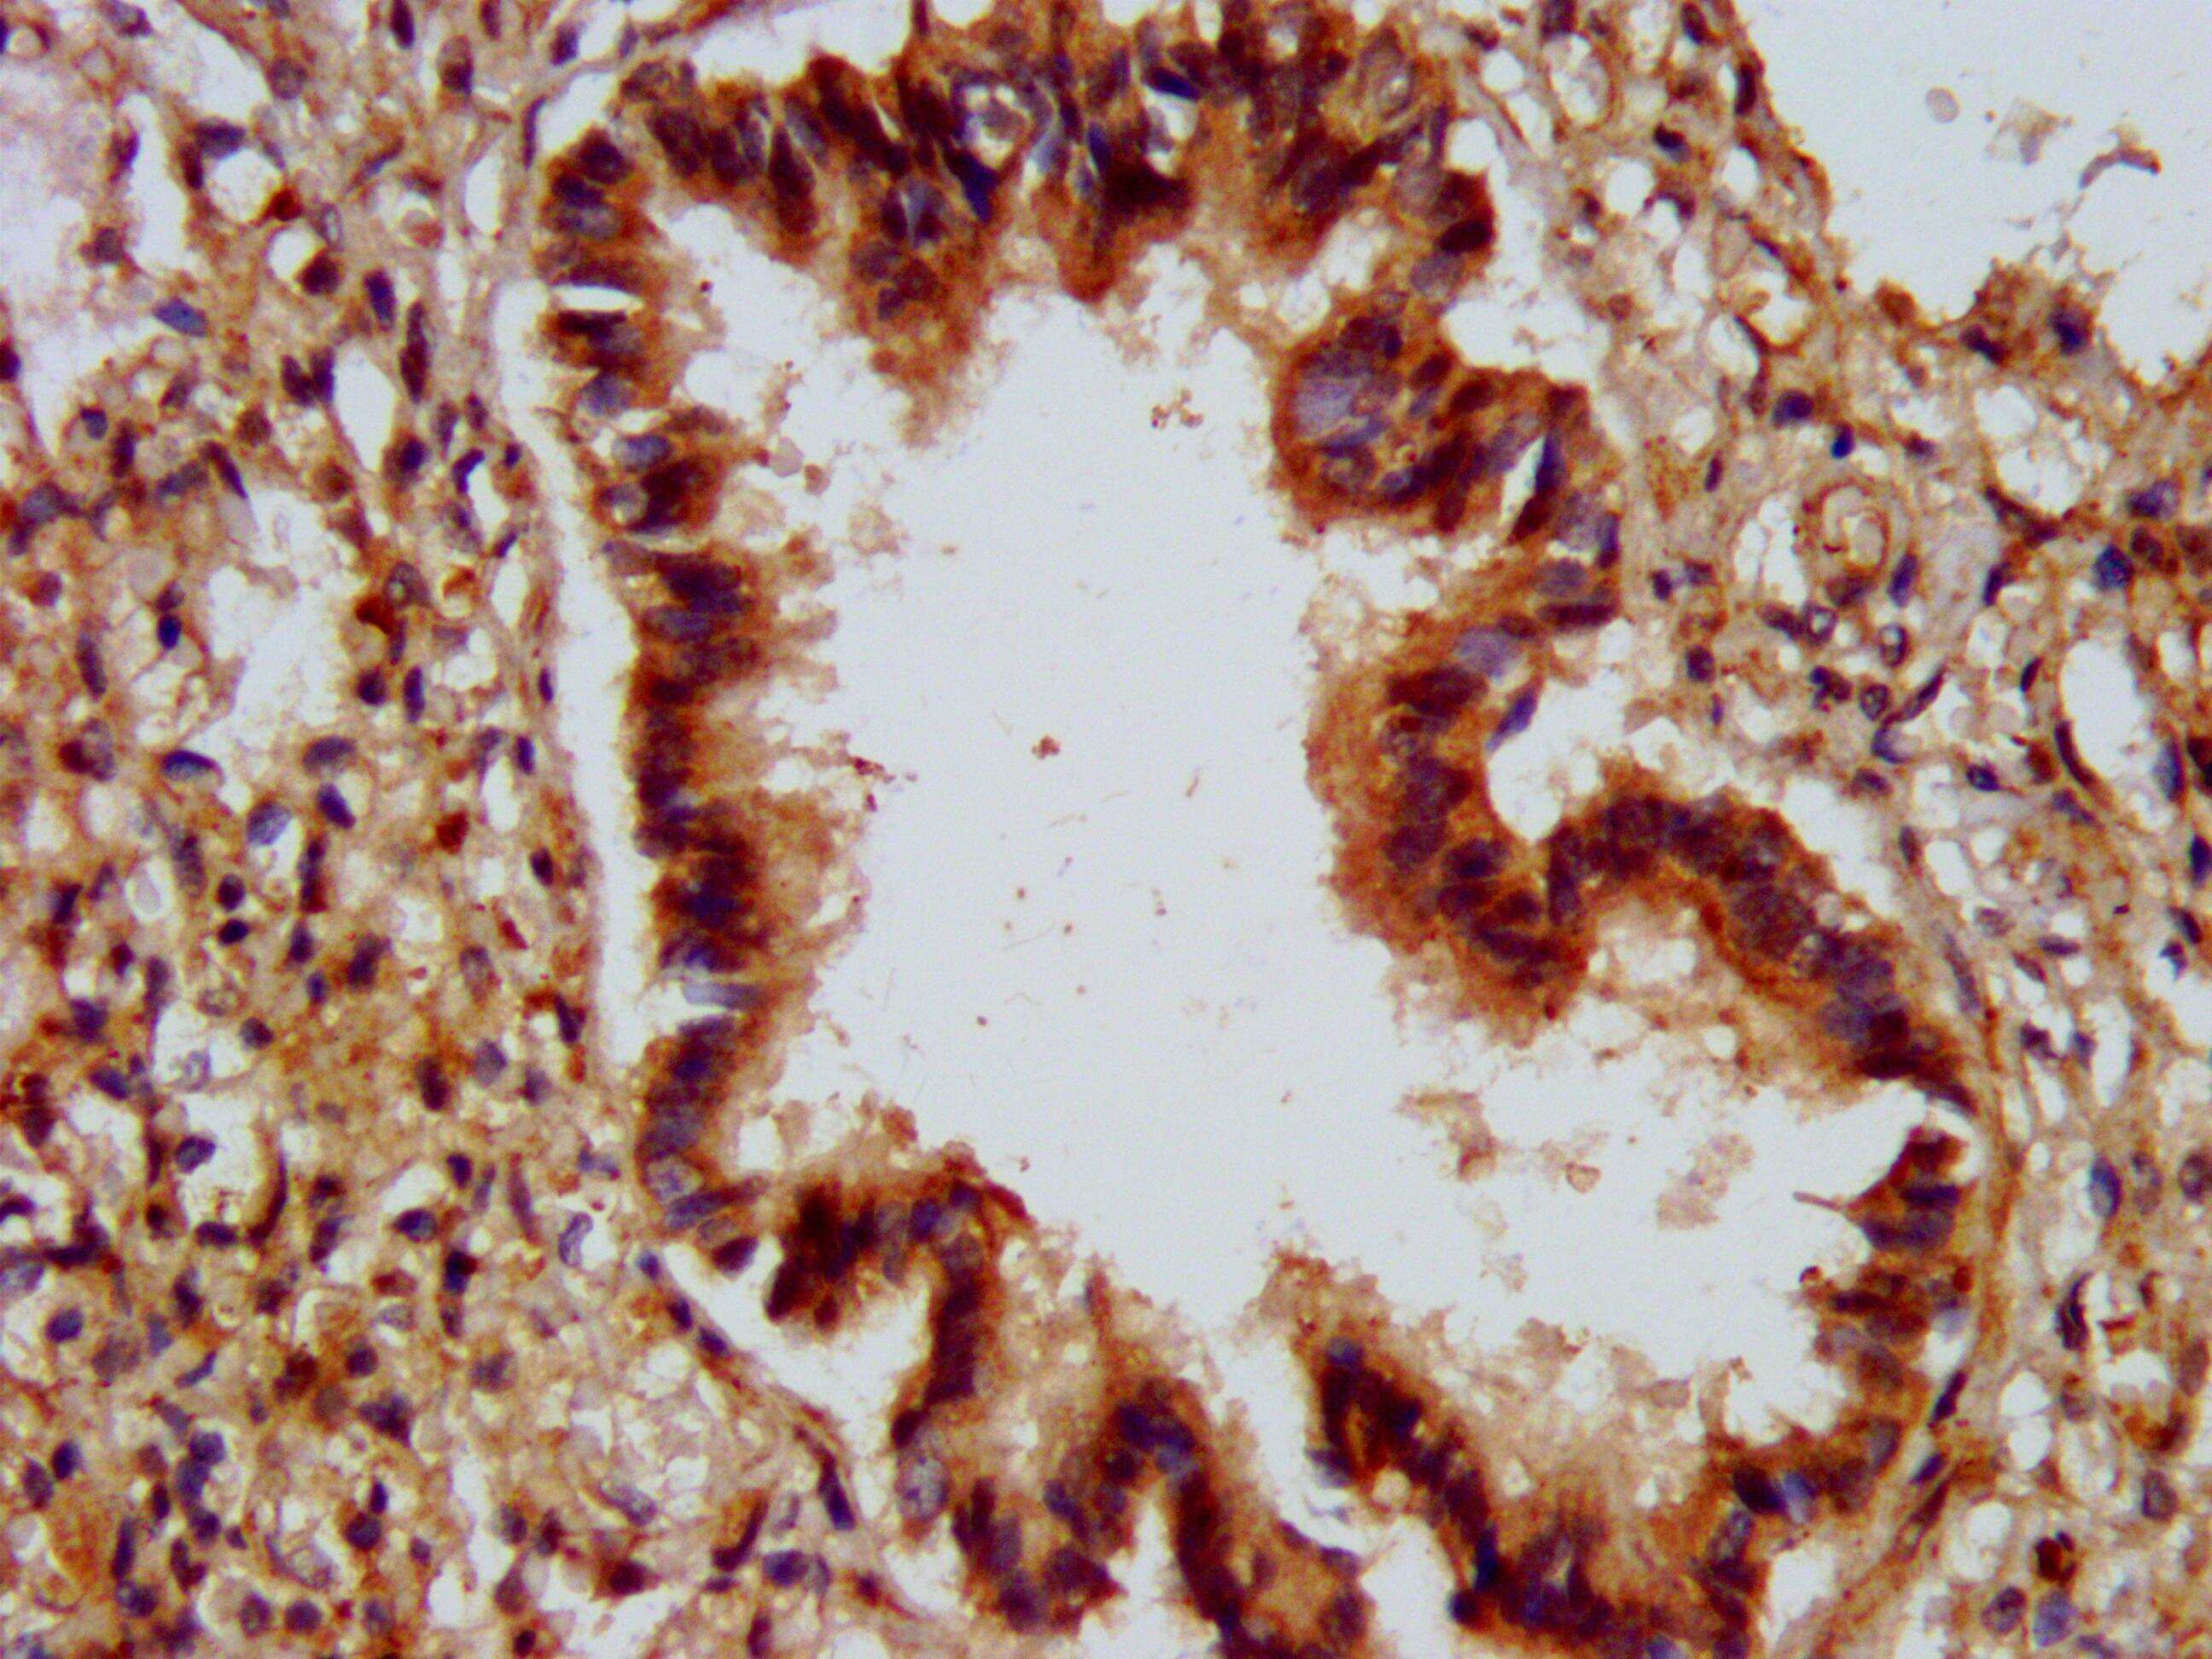

- Immunohistochemical analysis of ALG9 in paraffin embedded human lung tissue using a ALG9 polyclonal antibody (Product # PA5-98879) at a dilution of 1:300. After dewaxing and hydration, antigen retrieval was mediated by high pressure in a citrate buffer (pH 6.0). Section was blocked with 10% normal goat serum 30min at RT. Then primary antibody (1% BSA) was incubated at 4°C overnight. The primary is detected by a biotinylated secondary antibody and visualized using an HRP conjugated SP system.